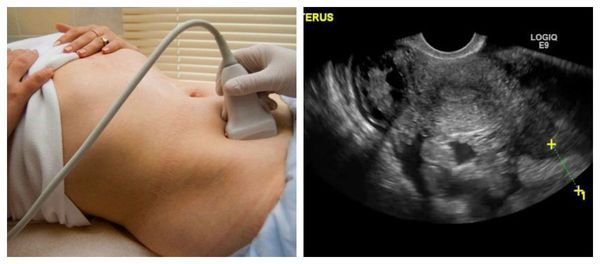

Добавлено: 13.03.2023, 07:04 Источник: Апоплексия яичника - кровоизлияние в яичник, сопровождающееся его разрывом и кровотечением в брюшную полость. Возникает вследствие патологических изменений сосудов (варикозное расширение, склероз) на фоне предшествующего воспалительного процесса. Чаще всего наступает в момент овуляции или в стадии васкуляризации желтого тела (середина и вторая фаза цикла). Провоцирующую роль играют травма, поднятие тяжести, бурное половое сношение. Симптомы и течение складываются из симптомов внутреннего кровотечения и болевого синдрома (острый живот). Диагностика представляет значительные трудности, так как сходные явления наблюдаются при нарушенной внематочной беременности. ![]() Среди всех острых заболеваний женской репродуктивной системы апоплексия яичника занимает третье место по частоте встречаемости. Чаще возникает у молодых женщин, но и в другом возрасте появление данного состояния не исключено. Апоплексия правого яичника случается в несколько раз чаще, чем левого, что объясняется его более обильным кровоснабжением — артерия, питающая правый яичник, отходит непосредственно от брюшной аорты (одного из крупнейших сосудов организма человека), а питающая левый яичник — от почечной артерии (сосуда гораздо меньшего диаметра). Апоплексия, как правило, возникает в середине менструального цикла в период овуляции, но также может наступить и во вторую фазу, особенно при наличии кисты (например фолликулярной кисты или кисты жёлтого тела). Причины апоплексии яичника Небольшое кровоизлияние в яичник в процессе овуляции — обычное явление. Но чтобы наступило острое состояние в виде апоплексии, должны подействовать определённые факторы: например, бурный половой акт, тупая травма живота или сильные физические нагрузки, т. е. любое действие, вызывающее выраженное повышение внутрибрюшного давления. Разрыв происходит при наличии застойных явлений в варикозно расширенных венах яичника или в склерозированных сосудах. Предрасполагающими факторами могут быть воспалительные заболевания органов малого таза. Также свою роль играют нарушения гормонального профиля — значительное увеличение и изменение гонадотропных гормонов: лютеинезирующего гормона, фолликулостимулирующего гормона и пролактина. Это приводит к избыточному кровенаполнению овариальной ткани. Нарушения функции вегетативной нервной системы в результате стрессов и психоэмоционального напряжения ведут к неправильному формированию жёлтого тела и образованию кист. К остальным факторам возникновения апоплексии яичника можно отнести: - неправильное положение матки (смещение в какую-либо сторону), например, из-за спаечного процесса в малом тазу; - сдавление сосудов, которое приводит к нарушению кровотока в яичнике; - давление на яичник опухоли; - стимуляция овуляции — увеличивает риск апоплексии яичника, так как влечёт за собой сбои развития жёлтого тела; - заболевания крови или приём лекарственных препаратов, ведущих к нарушению её свертывающей способности могут быть факторами длительного и обильного кровотечения. Также существуют данные о том, что к апоплексии яичника может быть генетическая предрасположенность (по гену GPIIIa, который ассоциируется с тромбозами различной локализации), которая чаще всего реализуется при ожирении, частых стрессовых ситуациях и сопутствующих заболеваниях, а также у курящих женщин Симптомы апоплексии яичника Апоплексии яичника всегда сопутствует боль. Возникает внезапно и остро, часто сразу после воздействия провоцирующего фактора. Боль может быть чрезмерно выражена, локализуется внизу живота на стороне поражения и может "отдавать" в бедро, поясницу, наружные половые органы и задний проход, а также усиливаться при движении. Боль при надавливании на переднюю брюшную стенку сначала односторонняя, затем распространяется на всю нижнюю часть живота. ![]() В редких случаях развитию острого болевого приступа предшествуют тупые незначительно выраженные боли, что может быть вызвано усиленным кровенаполнением яичника или нарастанием внутрияичникового давления. К болевой симптоматике может присоединяться невыраженное повышение температуры тела, напряжение мышц живота и тошнота, а также симптомы, обусловленные кровотечением в брюшную полость — нарастающая слабость, головокружение, бледность кожи, холодный липкий пот и спутанность сознания вплоть до его потери Классификация и стадии развития апоплексии яичника Условно выделяют две формы апоплексии яичника: болевую и геморрагическую. При болевой (псевдоаппендикулярной) форме преобладает боль, кровотечение выражено незначительно и быстро самостоятельно останавливается. Эта форма возникает, если в плоскость разрыва попал сосуд малого калибра. При геморрагической (анемической)форме преобладают симптомы нарастающей кровопотери — бледность кожи, слабость, вялость, головокружение, снижение артериального давления вплоть до потери сознания. Имеется выраженное или не очень обильное, но длительное кровотечение в брюшную полость, которое самостоятельно не купируется. Описана также смешанная форма, при которой сочетаются оба признака. В зависимости от выраженности кровопотери и симптомов заболевания принято выделять три степени тяжести: Лёгкая — незначительная кровопотеря (до 150 мл), отмечается лёгкая бледность кожных покровов; слабость и головокружение при перемене положения тела выражены незначительно; артериальное давление в пределах нормы. Средней степени — кровопотеря составляет от 150 мл до 500 мл, наблюдается бледность кожи, слабость, вялость, головокружение, снижение артериального давления. Тяжёлая — при большом объёме кровопотери (более 500 мл) резкая бледность кожи и слизистых, выраженное снижение артериального давления, нитевидный пульс, потеря сознания. В зависимости от степени тяжести лечащий врач выбирает тактику дальнейшего лечения апоплексии яичника Осложнения апоплексии яичника При несвоевременно оказанной медицинской помощи и большой кровопотери возможно резкое развитие геморрагического шока, основными клиническими симптомами которого являются резкая бледность кожи, слизистых оболочек, тахикардия и резкое падение артериального давления. Это крайне опасное для жизни острое состояние, при котором нарушается кровоснабжение тканей, ухудшается сердечный выброс, развивается полиорганная и полисистемная недостаточность. Если не лечить апоплексию яичника, то главным отдалённым последствием может стать спаечный процесс органов малого таза. Спайки — это сращения и тонкие тяжи из соединительной ткани, возникающие в брюшной полости между соседними органами. В основе возникновения спаечного процесса лежит раздражение брюшины (оболочки, покрывающей внутренние органы со стороны брюшной полости). Спайки формируются для защиты организма — они создают препятствие на пути изливающейся крови или воспаления и локализуют процесс. Однако образовавшиеся тяжи соединительной ткани сами становятся проблемой, поскольку мешают правильной работе внутренних органов и даже могут быть причиной бесплодия и внематочной беременности ![]() Диагностика апоплексии яичника При диагностике апоплексии яичника важны анамнестические данные (связь с предшествующим половым актом или физическим напряжением; середина или вторая половина менструального цикла), а также характер начала болей. Болевая форма заболевания характеризуется приступом болей, как правило, никуда не "отдающих", иногда они могут сопровождаться тошнотой или рвотой. Признаков кровотечения в брюшную полость нет. В случае этой формы необходима дифференциальная диагностика с острым аппендицитом. При осмотре на гинекологическом кресле живот болезнен при пальпации в подвздошной области, симптомов перитонита нет. Матка обычного размера, безболезненна, определяется несколько увеличенный яичник на стороне поражения. Своды влагалища глубокие, свободные. Необходимо проведение УЗИ органов малого таза. При его выполнении редко можно увидеть изменения в яичнике, но иногда обнаруживаются косвенные признаки патологии — небольшое скопление жидкости позади матки. В общем анализе крови при болевой форме можно выявить лишь небольшое повышение лейкоцитов. При геморрагической форме основными симптомами выступают признаки внутрибрюшного кровотечения (головокружение, слабость, обмороки). Боль часто иррадиирует в наружные половые органы, задний проход, крестец и ноги. При осмотре кожа бледная с холодным липким потом. Артериальное давление снижено, определяется частый пульс. При осмотре на гинекологическом кресле отмечается резкая болезненность в нижних отделах живота при пальпации, перитонеальные симптомы положительны в нижних отделах живота. Матка не увеличена, может отмечаться её болезненность, покачивания за шейку матки также вызывают резкую боль. На стороне поражения определяется болезненный яичник. Своды влагалища нависают. Такую форму апоплексии нужно дифференцировать с внематочной беременностью, при которой может быть задержка менструаций, прочие признаки беременности и, как правило, мажущие кровянистые выделения из половых путей. При этой форме апоплексии яичника обязательно проведение УЗИ, при котором определяется большое количество свободной жидкости в брюшной полости со структурами неправильной формы (кровяными сгустками). ![]() В общем анализе крови отмечается снижение уровня гемоглобина, а также незначительное увеличение лейкоцитов. При диагностике данной формы (при выявлении свободной жидкости в брюшной полости по УЗИ) необходимо проведение пункции брюшной полости через задний свод влагалища. Такая манипуляция позволяет подтвердить или исключить наличие крови в брюшной полости. Под общим обезболиванием или местной анестезией проводится прокол заднего свода влагалища иглой и набирается жидкость. Её характер оценивается врачом и позволяет определить тактику дальнейшего ведения пациентки. Одним из методов диагностики апоплексии яичника может быть диагностическая лапароскопия. Это малоинвазивная хирургическая операция, позволяющая получить более полную информацию о состоянии внутренних органов и разглядеть интересующий участок в мельчайших деталях. При необходимости сразу проводятся необходимые лечебные манипуляции, например коагуляция кровоточащего сосуда. ![]() Апоплексия яичника при лапароскопическом обследовании выглядит как приподнятое небольшое пятно до 0,5 см в диаметре с признаками кровотечения или прикрытое сгустком крови, либо же в виде жёлтого тела с разрывом, признаки кровотечения могут отсутствовать. Лечение апоплексии яичника Срочная госпитализация. При отсутствии выраженного внутреннего кровотечения и коллапса возможна консервативная тактика (покой, холод на низ живота). При нарастающих явлениях внутреннего кровотечения показана операция - лапаротомия, резекция яичника. Одновременно необходимо возместить кровопотерю (ретрансфузия, переливание донорской крови, кровезаменителей), при необходимости вводят сердечно-сосудистые препараты. Консервативное лечение возможно при болевой формы апоплексии яичника. Представляет собой назначение кровоостанавливающих и обезболивающих препаратов, а также витаминотерапии. Пациентке требуется наблюдение и покой. Также рекомендовано охлаждение нижних отделов живота и проведение УЗИ органов малого таза в динамике (через 12 часов). Наблюдение и лечение проводят в условиях стационара. В случае ухудшения состояния и появления признаков внутреннего кровотечения проводят хирургическое лечение. Хирургическое лечение показано пациенткам с геморрагической или смешанной формой апоплексии яичника. Оно может производиться лапаротомным (путём разреза) или лапароскопическим (эндоскопическим) доступом, в зависимости от обильности кровотечения, состояния пациентки и возможностей стационара. Приоритетно проведение операции лапароскопическим доступом, так как она не приводит к косметическим дефектам и позволяет достичь быстрой реабилитации. В ходе операции проводят коагуляцию или ушивание повреждённого сосуда. Если обнаруживается разрыв кисты яичника, то киста удаляется и ушивается яичник. К удалению яичника, как правило, не прибегают. Если в ходе операции в брюшной полости обнаруживают большое количество крови, то можно прибегнуть к аутогемотрансфузии. Это метод восполнения объёма циркулирующей крови своей же кровью, забранной из брюшной полости. В стерильных условиях кровь удаляют из живота, после чего её фильтруют и вводят внутривенно. Такой метод является наиболее физиологичным и позволяет быстрее восстановить показатели крови, чем при введении кровезамещающих растворов. В послеоперационном периоде проводят комплексное лечение, включающее лекарственные препараты и физиотерапию. Главной задачей является восстановление гормональных и обменных процессов, устранение причин, вызвавших патологию, проведение профилактики спайкообразования в брюшной полости. В раннем послеоперационном периоде используются: озонотерапия, магнитотерапия, электрофорез с лонгидазой и цинком В отдалённом послеоперационном периоде рекомендовано назначение комбинированных оральных контрацептивов для временного подавления овуляции и профилактики рецидива апоплексии или использование циклической витаминотерапии в сочетании с гестагенами. Так как существует связь апоплексии яичника и наличия воспалительных заболеваний органов малого таза, в некоторых случаях необходимо назначение курса антибиотикотерапии с последующей коррекцией биоценоза влагалища. |